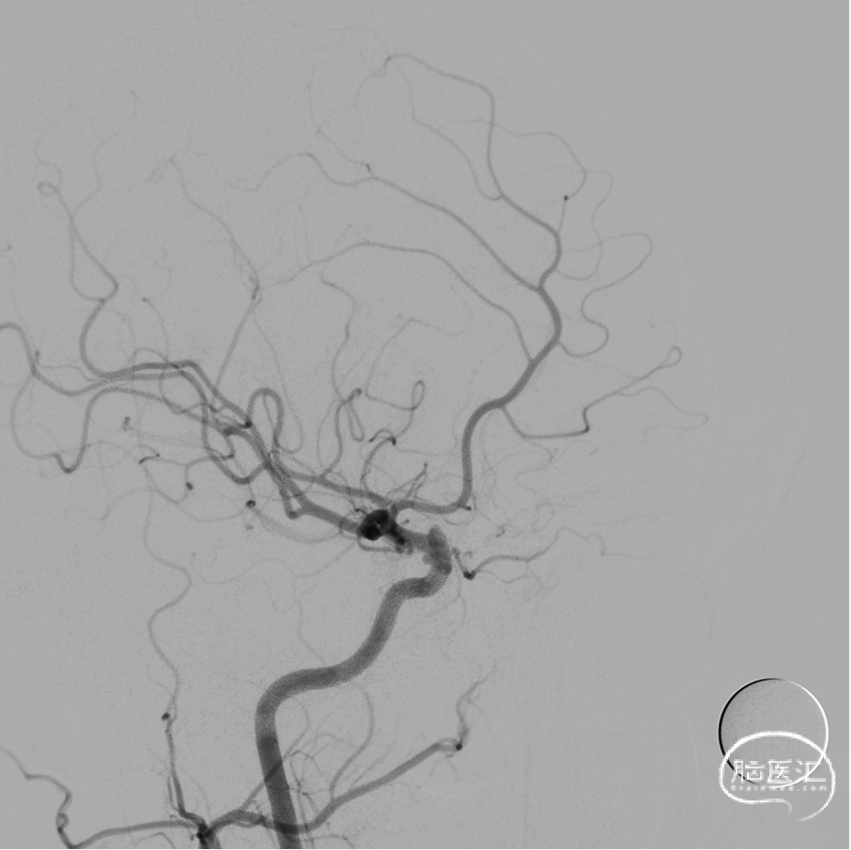

2021-12-20 脑血管造影:

左侧颈内动脉多发动脉瘤;右侧颈内动脉床突段动脉瘤。

LICA 多发动脉瘤,大小分别为3.09×3.79mm、1.73×1.73m及1.79mm×1.63mm,载瘤动脉远端直径为3.11mm,近端直径3.49mm。

RICA 床突旁动脉瘤 6.56×5.29mm ,载瘤动脉近段直径约3.66mm,远端直径3.40mm。